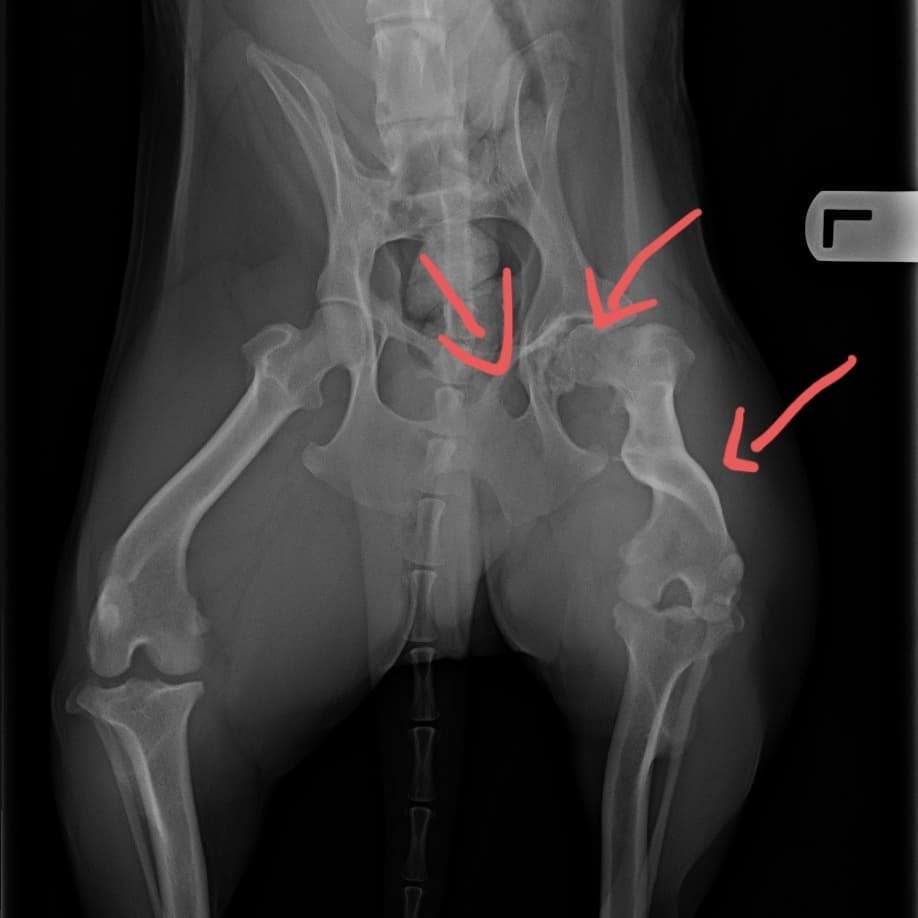

This is Schroeder. He's the sweetest little man. He had a vet visit yesterday. From the first day he was here, I could tell that he had an unusual gait (he walks funny) and so when he went to the vet yesterday for his checkup, vaccines, microchip etc, I requested x-rays.

You can see he's had a pretty bad injury. He was probably hit by a car. He had a pelvic fracture and a fractured femur :( all of which healed up on its own.

Because he had to compensate for the fractures, he also has an odd gait in his front as well. This is an old injury, we don't know when it happened. He's about 4 years old as per the vet, and his teeth are pretty wrecked. He also needs a dental at some point.